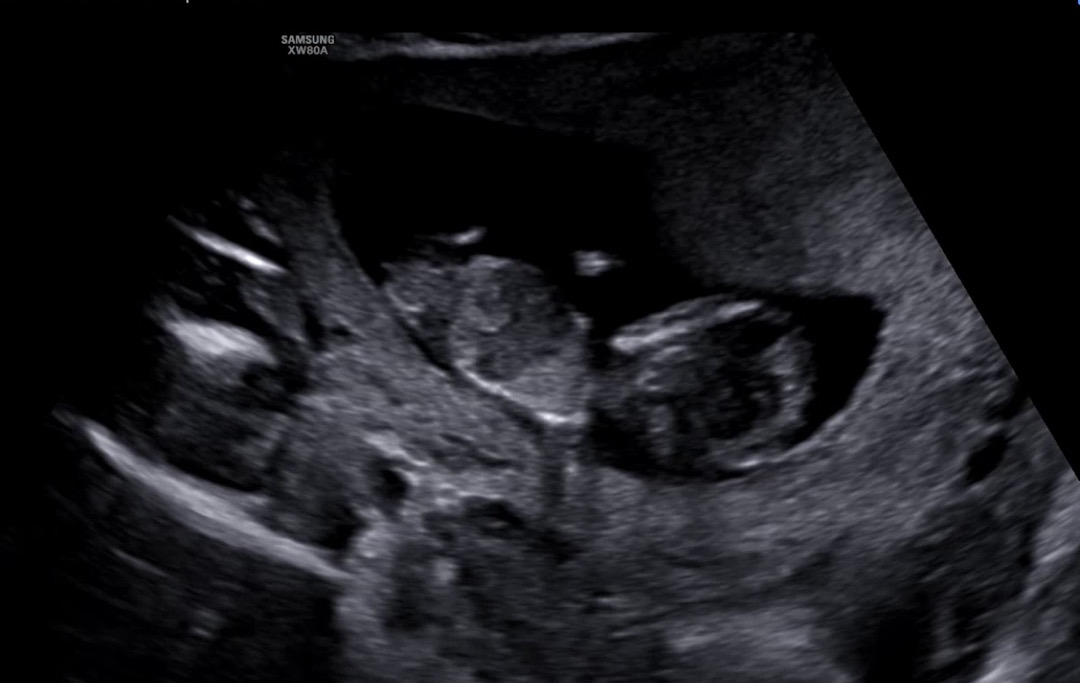

각도법 고수님들!!!

11주 4일입니다 ..... 안 보이는 거 알지만 .............. 도움 좀 주세요🙏🏻🙏🏻🙏🏻🙏🏻🙏🏻🙏🏻 제 눈에만 돌기가 보이나용? 원장님께선 입초하실때 저거 보이시는거는 그냥 탯줄이에요~ 하셨는데.... 마지막에 성별힌트 없죠...? 하니까 아직은 아니라구.

지금 각도법으로보셔도 틀릴가능성 높고 이 사진으로는 각도법도 잘 안보여요ㅠ